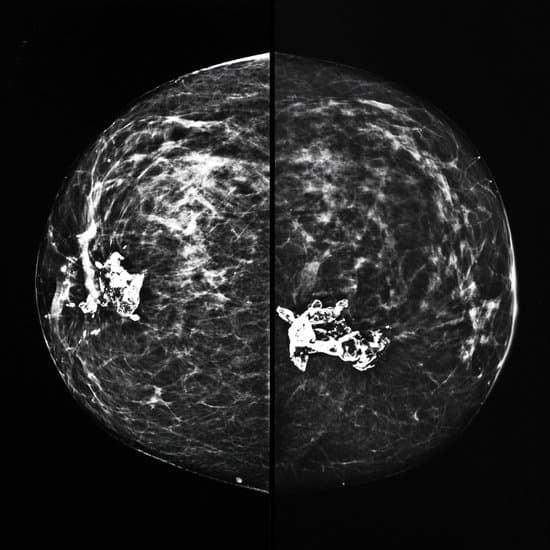

유방촬영술 결과 해석: 의심 (Suspicious, BI-RADS 4) 조직검사 권유

유방촬영술(맘모그래피)은 유방암 조기 발견을 위해 시행하는 대표적 영상검사입니다.

영상의학과 전문의는 BI-RADS (Breast Imaging Reporting and Data System)라는 국제 표준 분류 체계에 따라 결과를 해석합니다.

"의심 (Suspicious, BI-RADS 4)"의 의미

영상에서 발견된 병변이 악성 가능성을 배제할 수 없는 경우

악성 가능성 범위: 약 2% ~ 95% → 매우 넓음

따라서 단순 영상만으로는 확실히 양성/악성을 구분하기 어려움

세부적으로 4A (낮음, 210%) / 4B (중간, 1050%) / 4C (높음, 50~95%) 로 나누어 평가하기도 함